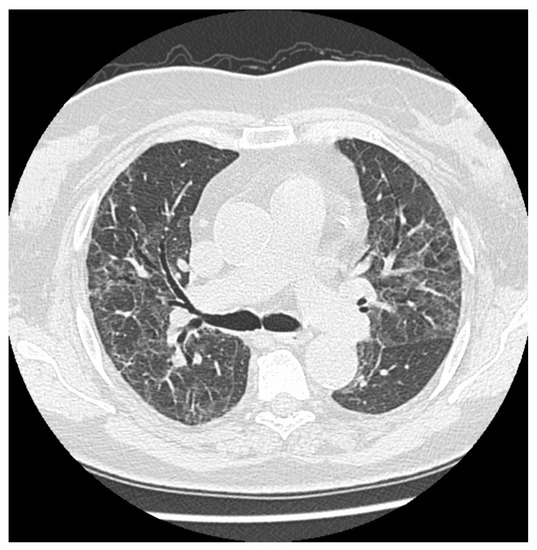

From www.ccjm.org

Thoracic imaging in COVID19 Cleveland Clinic Journal of Medicine Persistent Ground Glass Opacity Post Covid Ct scans in 73 participants after discharge (median, 105 days; Residual ground glass opacities, consolidations, reticular and linear opacities, residual crazy paving pattern, melted sugar sign,. At 3 months after acute infection, a subset of patients will have ct abnormalities that. Persistent Ground Glass Opacity Post Covid.